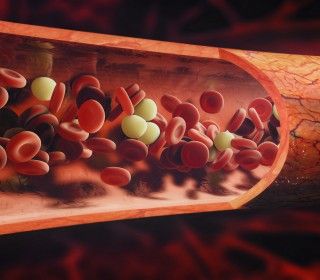

Osocze bogatopłytkowe to prawdziwa bomba odżywcza dla skóry i włosów. Odmładza, regeneruje, skutecznie spowalnia procesy starzenia się. To dlatego osocze bogatopłytkowe pokochały osoby na całym świecie. Nie wszyscy jednak wiedzą, że separat można pozyskać na kilka sposobów lub że da się nim leczyć łysienie. Poznaj cztery fakty dotyczące osocza oraz zabiegu z jego wykorzystaniem.

Osocze bogatopłytkowe to prawdziwa bomba odżywcza dla skóry i włosów. Odmładza, regeneruje, skutecznie spowalnia procesy starzenia się. To dlatego osocze bogatopłytkowe pokochały osoby na całym świecie. Nie wszyscy jednak wiedzą, że separat można pozyskać na kilka sposobów lub że da się nim leczyć łysienie. Poznaj cztery fakty dotyczące osocza oraz zabiegu z jego wykorzystaniem.

- Mezoterapia i intradermoterapia osoczem bogatopłytkowym to najskuteczniej obecnie odmładzający zabieg (oczywiście poza własnymi komórkami regeneracyjnymi i macierzystymi pacjenta). Pozwala w krótkim czasie uzyskać delikatny lifting i promienny wygląd – mówi dr Urszula Brumer, lekarz medycyny estetycznej i właścicielka warszawskiej kliniki Medycyna Młodości. - Płytki krwi zawierają czynniki wzrostu, stymulujące komórki skóry do samoodnowy. Zatem w efekcie podania osocza bogatopłytkowego w skórę, staje się ona gładsza, bardziej elastyczna i wyraźnie młodsza. Wygładzają się drobne zmarszczki, a twarz nabiera blasku.

Ponieważosocze bogatopłytkowejest preparatem pozyskiwanym z krwi pacjenta, nie ma ryzyka reakcji uczuleniowej a zabieg jest całkowicie bezpieczny. Zabieg nazywany jest również Autologiczną Odnową Komórkową (ACR – Autologous Cellular Regeneration), gdyż regeneracja komórek skóry zachodzi dzięki działaniu własnych czynników wzrostu i substancji przeciwzapalnych.

Osocze pozyskane z krwi może mieć różne stężenie płytek krwi, a wszystko to w zależności od metody pozyskania osocza, na którą się zdecydujemy. Jedną z nich jest metoda prof. Ceccarelli-Garcia, nazywana również Full Face Regeneration. Umożliwia ona kompleksowe odmłodzenie wszystkich tkanek twarzy w sposób naturalny, komfortowy i bezpieczny dla pacjenta. Zabieg z użyciem tej metody zaczyna się od miejscowego znieczulenia i pobrania niewielkiej ilości krwi pacjenta (około 32 mililitry) do probówki. Następnie krew poddajemy wirowaniu w medycznej wirówce laboratoryjnej w celu uzyskania osocza (około 15 ml), czyli koncentratu z płytkami krwi, zawierającego czynniki wzrostu, które będą pobudzać skórę do regeneracji.Uzyskany koncentrat ma barwę złocistą i działa niczym eliksir młodości. Wciągamy go do strzykawki i ostrzykujemy twarz lub/i inne okolice ciała pacjenta. Osocze aktywowane jest wewnątrz, a nie na zewnątrz skóry, co daje najlepsze efekty odmładzające.

O ile metoda prof. Cecarelli Garcia polega na pozyskaniu osocza o stężeniu płytek krwi 3 razy większym niż w krwi pełnej, o tyle inna metoda, nazwana Angel System polega na pozyskaniu osocza o stężeniu płytek krwi 6-8 razy większym niż w krwi pełnej, a metoda Prosys – na pozyskaniu osocza o stężeniu płytek krwi 5 razy większym. Co zatem wybrać? Wiele zależy zatem od stopnia problemu, z jakim się zmagamy, ale warto podkreślić, że im większe stężenie płytek krwi, tym uzyskujemy szybszy efekt. W praktyce zabieg Angel System częściej wybierają panowie cierpiący z powodu łysienia (ponieważ oczekują szybkich efektów, bez konieczności wykonywania zabiegu w seriach), zaś kobiety chcące odmłodzić twarz – metodę prof. Cecarelli Garcia (ponieważ nie przeszkadza im przypominanie zabiegu co jakiś czas), a osoby chcące usunąć blizny – metodę Prosys (ponieważ chcą uzyskać maksymalnie skondensowane osocze redukujące blizny). Nie ma jednak na to reguły, która metoda jest lepsza. Każdego pacjenta traktujemy indywidualnie, bo wiemy, że każdy ma inne potrzeby – wyjaśnia dr Urszula Brumer.

W jakich przypadkach warto zdecydować się na zabieg osoczem bogatopłytkowym? Ta metoda odmładzania doskonale sprawdza się, kiedy chcemy np.: wygładzić skórę, zredukować blizny potrądzikowe i przebarwienia, poprawić opadający po czterdziestym roku życia kontur twarzy, zwiększyć napięcie skóry na szyi lub wyleczyć nadmierne wypadanie włosów – tak u mężczyzn, jak i u kobiet. Jak podkreśla dr Urszula Brumer, osocze bogatopłytkowe podane w skórę uruchamia proces, którego zadaniem jest stymulacja komórek skóry do namnażania oraz pobudzanie fibroblastów do wytwarzania nowego kolagenu. W rezultacie uzyskujemy regenerację i odnowę skóry, jej nawilżenie i odmłodzenie.

Co istotne, osocze bogatopłytkowemożna wstrzykiwać do skóry na różne sposoby. Z zastosowaniem klasycznej mezoterapii, bądź też liniowo, wzdłuż zmarszczki lub fałdu skóry. Zabieg można jednocześnie łączyć z innymi zabiegami medycyny estetycznej takimi, jak: peelingi, mikrodermabrazja czy zabiegi laserowe, co zawsze prowadzi do uzyskania jeszcze lepszego efektu ostatecznego.

Dużo skuteczniejszym rozwiązaniem jest jednak skorzystanie z zabiegu z osoczem bogatopłytkowym. Czynniki wzrostu zawarte w płytkach krwi, podane do skóry głowy, pobudzają cebulki do wytwarzania nowych i mocniejszych włosów. Mezoterapia z użyciem osocza jest więc zabiegiem stymulującym komórki skóry i jej przydatki, a poza tym korzystnie wpływającym na poprawę krążenia w naczyniach włosowatych. Choć sam zabieg nie należy do najprzyjemniejszych, to jest za to krótki i skuteczny. Uzyskuje się widoczny odrost i lepszą jakość włosów. Zaleca się wykonanie serii 3 zabiegów powtarzanych co 1-2 miesiące. Jedna wizyta trwa ok. 30 minut, a ślady ukłucia igłą znikają w ciągu kilku godzin. Zadziwiająco pozytywne efekty sprawiają, że zaczynamy rozumieć, dlatego osocze bogatopłytkowe nazywane jest odżywczo-stymulująca bombą oraz dlaczego jego popularność wciąż rośnie.

Osocze bogatopłytkowe to prawdziwa bomba odżywcza dla skóry i włosów. Odmładza, regeneruje, skutecznie spowalnia procesy starzenia się. To dlatego osocze bogatopłytkowe pokochały osoby na całym świecie. Nie wszyscy jednak wiedzą, że separat można pozyskać na kilka sposobów lub że da się nim leczyć łysienie. Poznaj cztery fakty dotyczące osocza oraz zabiegu z jego wykorzystaniem.

Osocze bogatopłytkowe to prawdziwa bomba odżywcza dla skóry i włosów. Odmładza, regeneruje, skutecznie spowalnia procesy starzenia się. To dlatego osocze bogatopłytkowe pokochały osoby na całym świecie. Nie wszyscy jednak wiedzą, że separat można pozyskać na kilka sposobów lub że da się nim leczyć łysienie. Poznaj cztery fakty dotyczące osocza oraz zabiegu z jego wykorzystaniem. Fakt 3 – osocze można wstrzykiwać do skóry na różne sposoby